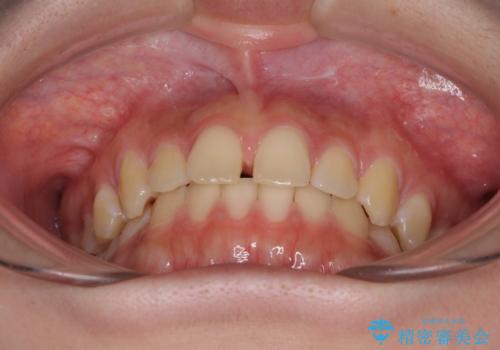

前歯のすきっ歯を治したい インビザラインによる矯正治療

- 上顎前歯の隙間を気にして来院された患者様です。

目立たない装置を希望とのことで、インビザラインを用いて矯正治療を行うこととしました。

最終的には隙間は全て閉じ、綺麗な仕上がりとなりました。